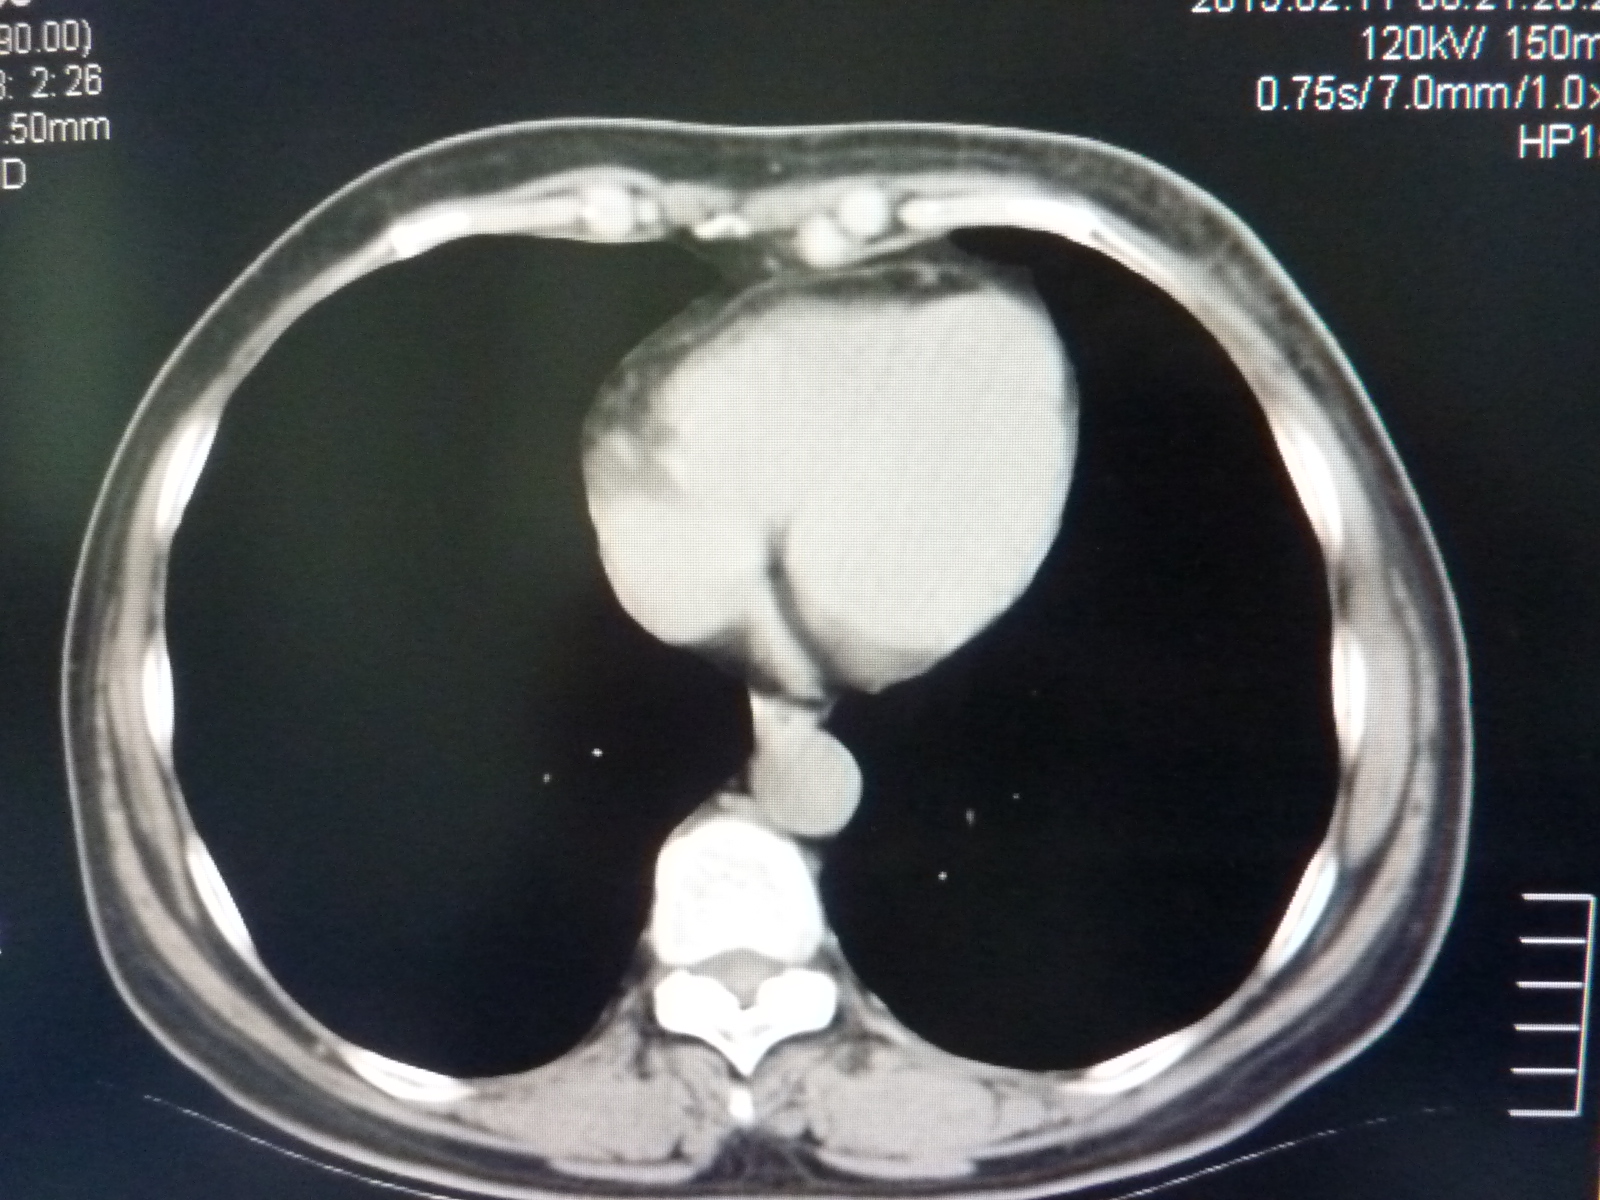

CT49913:女,58,左乳腺触及包块,质硬,感觉疼

本帖最后由 cefcmj 于 2015-2-13 07:38 编辑 怎么看着是感染,有肿瘤没?

未见块

增生